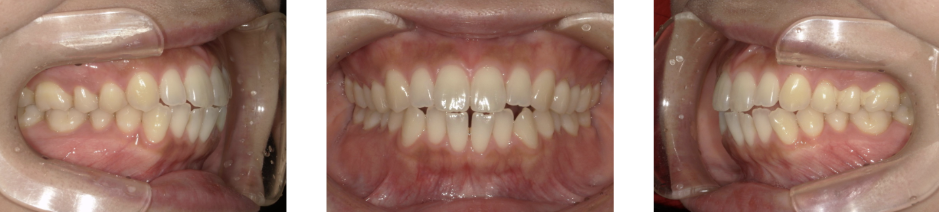

Before Photo

Before

After Photo

After

主訴

出っ歯 口元が出ている

治療期間

1年10か月

料金

相談料0円、検査料33,000円、動的矯正治療費990,000円、調整料110,000円、保定装置料5,500円x5枚(必要枚数)

治療概要

上下の個々の歯の大きさに対して、上下の顎が共に小さく、歯が並ぶ余地が不足したために、前歯が押し出されて出っ歯が生じている。

改善には、上下左右の第一小臼歯を抜歯して空隙を作り、前歯を後退させた。

矯正での歯の移動のリスクとして歯根吸収、歯肉退縮、歯髄怪死が考えられます。

保定装置の装置を怠ると隙間が生じてくる可能性があります。